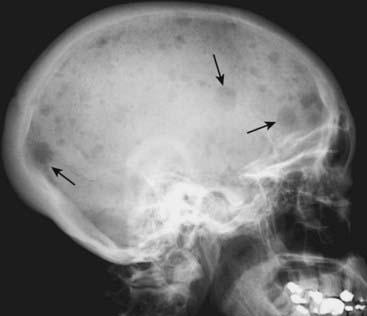

image

Figure 21-3 Diffuse metastatic disease from carcinoma of the prostate.

The bones are diffusely sclerotic. You can no longer see the normal trabeculae or the junction between the medullary cavity and the cortex as the medullary cavities have been filled in with osteoblastic metastatic disease that obscures these normal boundaries and increases the overall bone density. Contrast this picture with that of Paget disease of the pelvis (see Fig. 21-12).